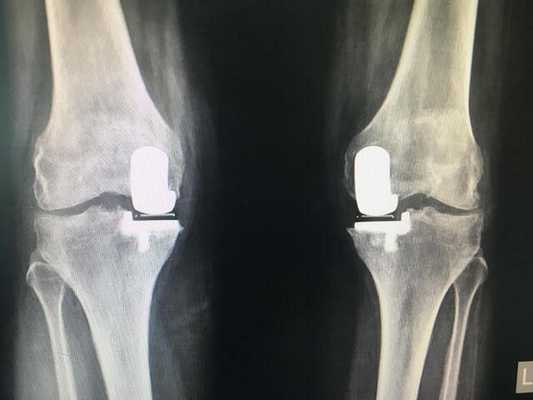

Типы протезов и связанные с ними методики

Вы уже знаете, что бывает полное и частичное эндопротезирование коленного сустава, где в первом случае лечение подразумевает полноценную замену суставных поверхностей, а во втором - имплантацию поврежденного участка одного из мыщелков. Соответственно, протезы классифицируются на тотальные, одномыщелковые и ревизионные для замены импланта.

- После постановки однополюсной системы максимально сохраняется собственный костно-хрящевой сегмент и не затрагиваются связки, кстати, они должны быть в хорошем состоянии.

Одномыщелковая замена сустава на рентгене.

Сравнение двух типов операций.

Одномыщелковое протезирование подразумевает срок службы небиологического устройства максимум 7 лет. Тотальное замещение предусматривает время службы вживленного механизма от 15 лет. Ревизионное переносится сложнее, а риск инфекции и других негативных явлений почти в 2 раза выше, чем после первичной операции.